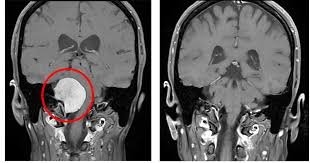

A Petroclival Meningioma is a rare type of skull base tumor that arises from the meninges near the junction of the petrous bone and the clivus — an area deep within the skull, close to the brainstem and cranial nerves. Although usually benign (non-cancerous), its location makes surgical treatment extremely challenging.

Accurate diagnosis requires detailed neuroimaging studies. MRI with contrast is the gold standard to identify the tumor’s size, location, and its relationship to nearby nerves and vessels. CT scans help assess involvement of surrounding bones at the skull base.